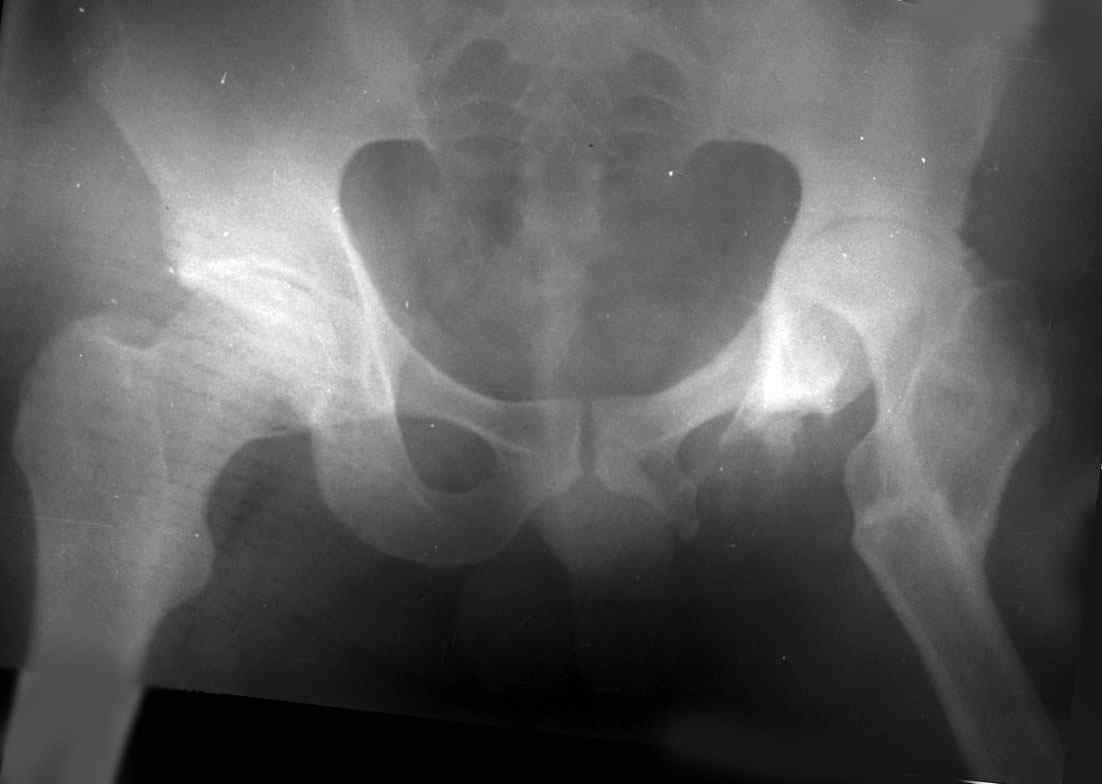

Moghno i tak kak sdelali my: pelvic support + tibial and equinus correction .

Слайд 1

Слайд 2

Слайд 3

Слайд 4

Devushka predstavlennaya na snimke nachala s LLD 9 cm, valgus deformation of the tibia, huge Trendelenburg( vidno na snimke).

Seichas : no LLD ,no Trendelenburg, reasonable hip motion.A samoe glavnoe ei ne predstoit kaghdye 10-15 let delat revision THR.

остеотомии. Я представил Р-граммы больных с неудачными р-ми после остеотомий.